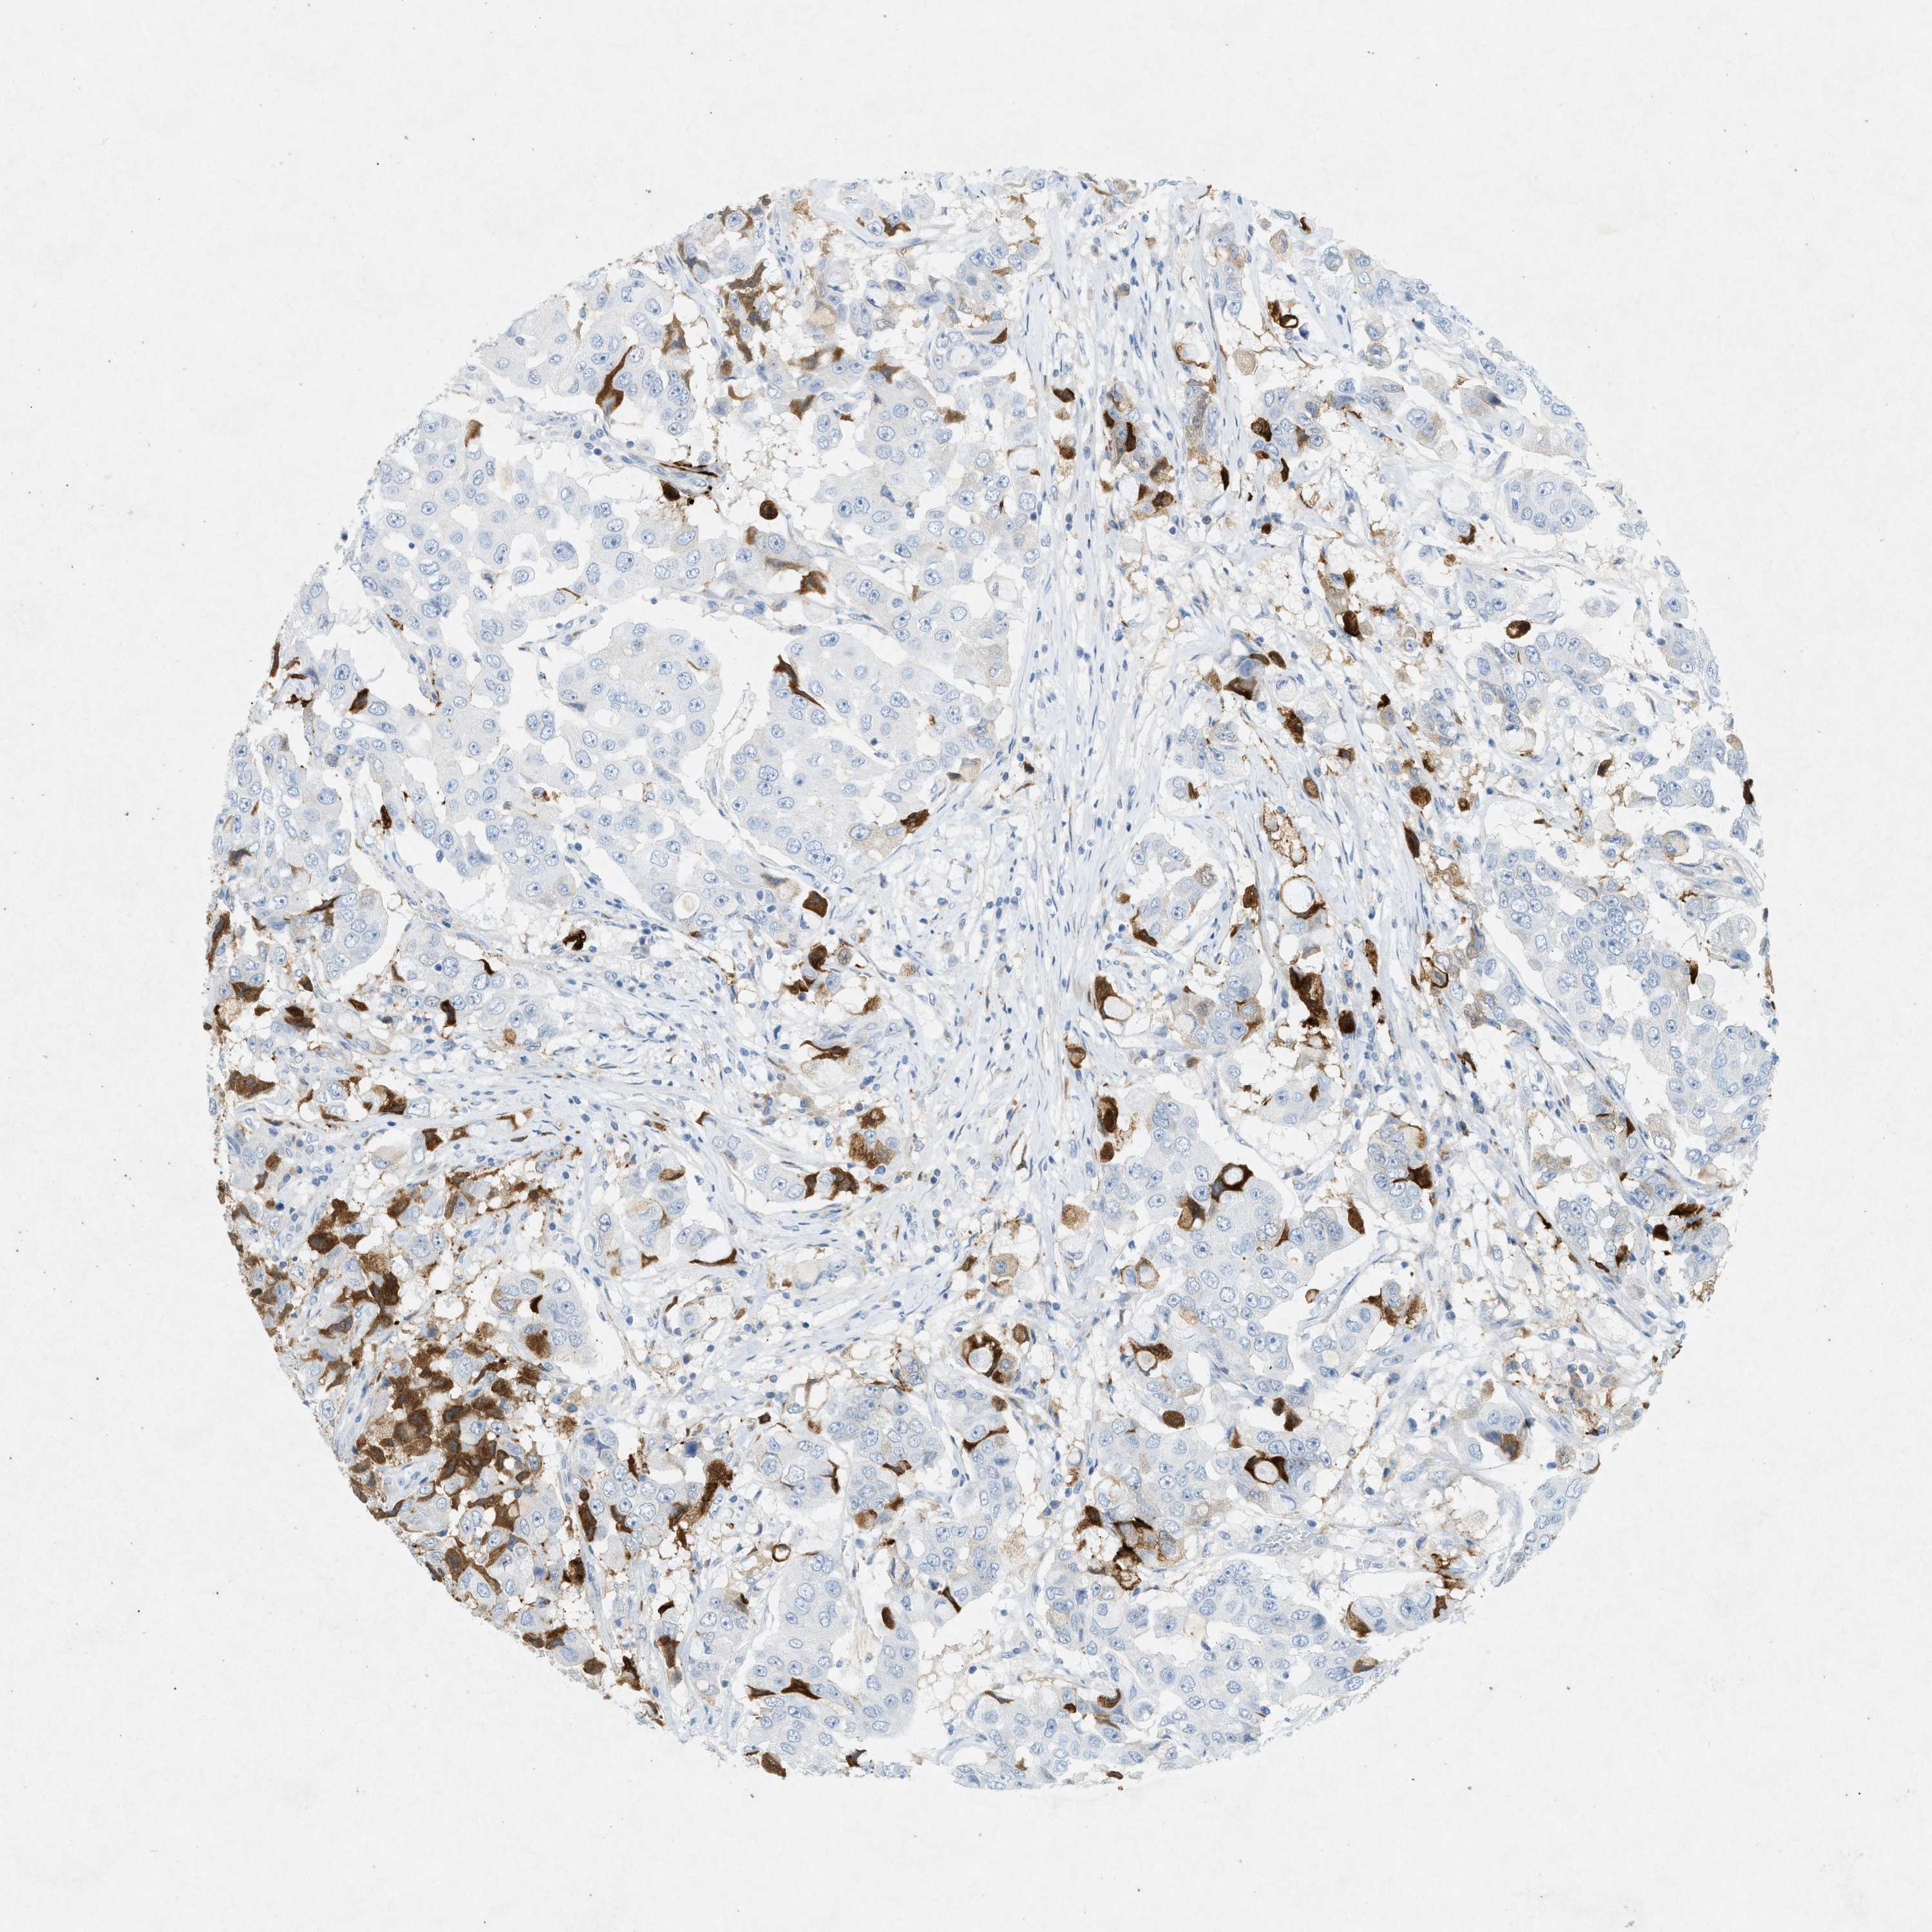

CANCER BREAST CANCER Show tissue menu

BRCA TCGA BRCA VALIDATION PROTEIN EXPRESSION